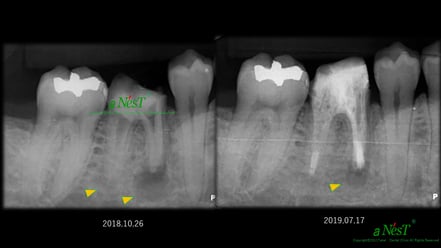

他院で抜歯と診断された症例です。友人の歯科医師の紹介で遠方から通院されました。初診時(左図)には、楔印で示すように、歯の根の先に黒い影が明瞭に写っています。が治療開始から8ケ月後(右図)では、黒い影は消えたり縮小しています。

歯の根の先の黒い影も消え(左図)、(手前は完全に消えていないが、完全な縮小傾向と症状がない)たので、クラウンを装着するための型採りをします。

右図の楔印は破折線です。破折線は特殊な方法で修復しています。